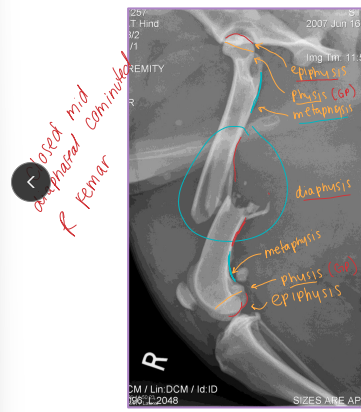

Fracture Classification

Location:

Spine, skull, joints: require special imaging (CT, oblique, stress views)

Long bones: Epiphysis, Physis (growth plate), Metaphysis, Diaphysis, Articular

Salter-Harris = Physeal Fractures

Common in young animals (open physes)

Femur Fractures

Capital Physis: Salter-Harris I, skeletally immature

Dt: AP & frog-leg radiographs